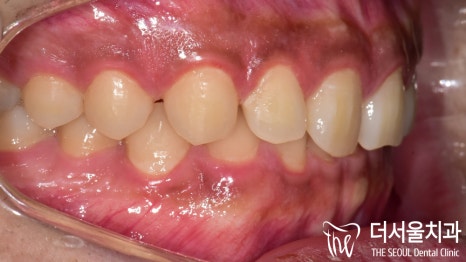

1. 초진

앞에서 봤을 때

하악 전치부들이 상악 전치부에

많이 가려져 있는 것을 볼 수 있습니다.

앞니는 양 옆으로 벌어진 형태였으며

양쪽 절단연이 비대칭적인

모습을 갖고 있네요.

어금니 뒤쪽은 배열에서 벗어나

삐뚤어져 있는 총생을 갖고 있었습니다.

이를 크라우딩(crowding)이라 부릅니다.

맨 뒤에있는 어금니가 올바른 맞물림이 아니라

바깥 쪽으로 뻐드러져 교합이 되지 않고 있었는데요.